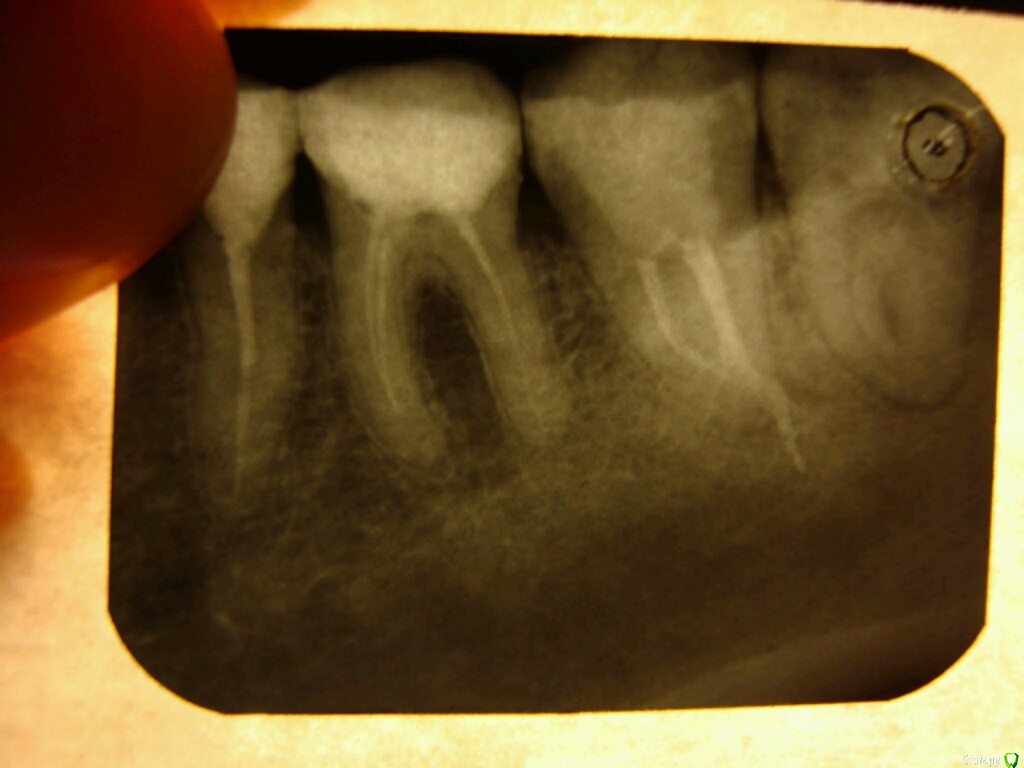

арбузова Опубликовано 7 июня, 2017 Автор Поделиться Опубликовано 7 июня, 2017 (изменено) Вот зуб) Изменено 7 июня, 2017 пользователем арбузова Ссылка на комментарий

red_butler Опубликовано 8 июня, 2017 Поделиться Опубликовано 8 июня, 2017 Вот зуб)Я бы этот зуб удалил Ссылка на комментарий

red_butler Опубликовано 9 июня, 2017 Поделиться Опубликовано 9 июня, 2017 почему?требуется повторное лечение корневых каналов с последующим протезированием Ссылка на комментарий

арбузова Опубликовано 9 июня, 2017 Автор Поделиться Опубликовано 9 июня, 2017 Так плохо полечили? При увеличении, вроде, в каналах какое-то наполнение видно. Ссылка на комментарий

арбузова Опубликовано 4 июля, 2017 Автор Поделиться Опубликовано 4 июля, 2017 Не подскажете, я так и не поняла, что у меня с зубом? Каналы не все запломбировали? Киста? Или чего ещё? Ссылка на комментарий

St. Опубликовано 6 июля, 2017 Поделиться Опубликовано 6 июля, 2017 Не подскажете, я так и не поняла, что у меня с зубом? Каналы не все запломбировали? Киста? Или чего ещё? За пределами корня зуба воспаление( то что вы назвали "киста"), потому что каналы заполнены материалом не очень плотно и "продезинфицированы" недостаточно. Все дело усложняется тем что зуб находится далеко, да и впринципе 8 зубы чаще всего имеют сложное строение каналов и в условиях муниципальной поликлиники адекватно их полечить мягко говоря непросто. Поэтому если оставить как есть , то в любой момент как только иммунитет ослабнет зуб разболится, еще и щека припухнуть может. Поэтому Я бы этот зуб удалил А перелечивать как положено это сложно, дорого и долго. И в случае 8 зубов чаще всего не имеет смысла из рациональных соображений. 2 Ссылка на комментарий